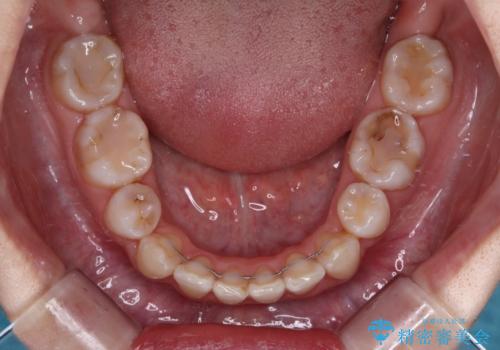

八重歯のためずれていた上下の正中をほぼ一致する位置に整えることができました。

重なって汚れの溜まりやすかった部分も改善され、大変満足していただけました。